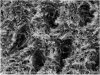

There are several advantages of using SDF in dental treatment. First, it showed an antimicrobial activity against mono-species, dual-species, and multi-species cariogenic biofilm.14-16 Silver ions are bactericidal metal cations that inhibit biofilm formation.17 Studies have indicated that silver interacts with sulfhydryl groups of proteins and DNA, thus altering hydrogen bonding and inhibiting respiratory processes, DNA unwinding, cell-wall synthesis, and cell division.18 At the macro level, these interactions affect bacterial killing and inhibit biofilm formation.17 Second, fluoride promotes caries lesion remineralization. Fluoride has been indicated to react with hydroxyapatite and generate calcium fluoride, which is a reservoir of fluoride, and facilitate further remineralization.19 An ex vivo study reported surface microhardness of the surface layer of the arrested caries after SDF applications was comparable with the unaffected sound dentin20 (Figure 1 and Figure 2). This is consistent with another study, in which a high remineralized zone was observed on the surface of arrested caries from exfoliated teeth with SDF treatment21 (Figure 3 and Figure 4). Third, its application procedures are simple and do not require injection or drilling, and the treatment does not involve expensive support infrastructure equipment such as piped water and electricity. The simplicity of the treatment is conducive to treating caries in apprehensive young children who may have intense dental fear, uncooperative patients with special needs, or elderly patients who have difficulty adapting to traditional dental care. It also allows trained workers to deliver the treatment to people who live in the area but who may not be able to easily access dental service.22 Patient compliance and satisfaction is often good when the patient is provided a clear explanation of the treatment outcome.23,24 Finally, the cost of SDF treatment is low and should be affordable in most communities.

Fig 4. Scanning electron microscope (SEM) images of the dentin carious lesions: surface morphology of active carious lesion. (image from Mei, et al, 2014, ref 21 [reprinted with approval])

Figure 4